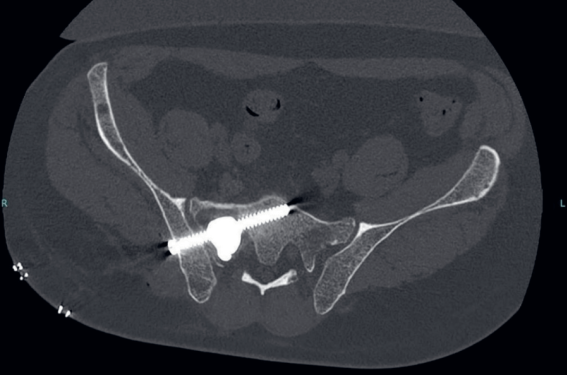

Consolidation osseuse en radiologie : il n’y a pas que la cimentoplastie !

À l’heure actuelle, près d’un patient métastatique sur cinq présente une localisation osseuse secondaire(1). La ceinture pelvienne constitue le deuxième site de localisation préférentielle, après le rachis, soit un peu plus de 10 % des patients avec une néoplasie métastatique sur un site osseux(1,2). Parmi ces patients, entre 20 et 50 % d’entre eux selon les études présenteront une complication à type de fracture pathologique. Celle-ci entraîne une dégradation de la qualité de vie des patients pouvant aller jusqu’à une impossibilité de mise en charge.

À la différence du rachis, où les contraintes en compression sont les seules qui s’exercent, l’anneau pelvien reçoit des contraintes plus complexes, en particulier de torsion et de tension, afin de transmettre les forces du rachis aux membres inférieurs, et inversement (3). La complexité des...